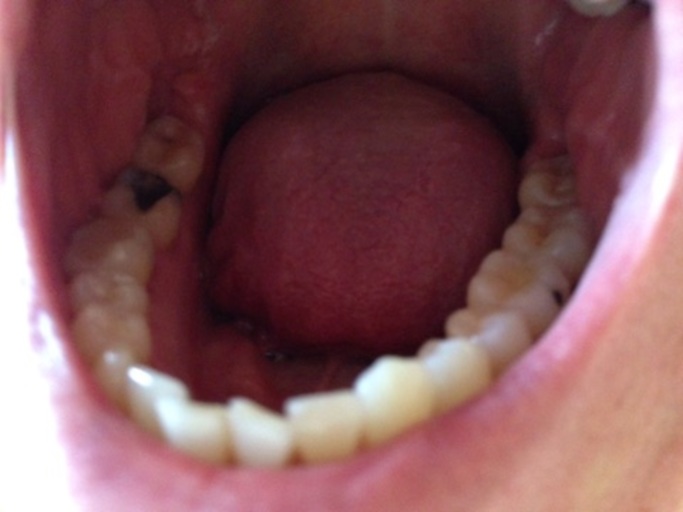

Big hole in tooth

I have a big hole in my tooth that just takes up the middle of my tooth. I don't want to have my tooth out as I have left it for a few weeks and Its going smaller, I want to know if I can have a filling and why is it getting smaller? I don't think there's a nerve it tooth anymore. P.s: there's no pain?